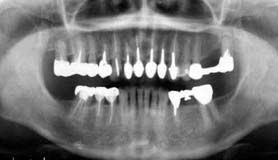

![]() |

| 図3.初診時(1997年7月)のオルソパントモグラフ。 | 図4.初診時口腔内。 |